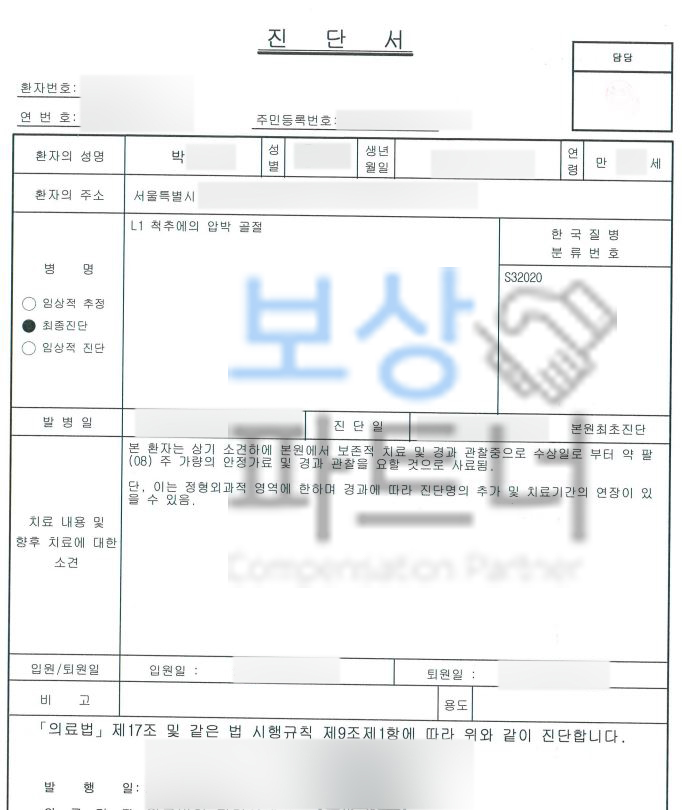

보상파트너로 문의해주셨던 서울시 거주 박@@님 또한 무거운 책을 드시다가 허리를 삐끗하셨다고 했는데요, 계속된 통증에 병원에 내원하여 Mri 등 정밀 검사를 받으셨고 진단 결과

L1 척추 요추압박골절

S32020 진단받으셨습니다. 박@@님은 수상일로부터 약 8주간 TLSO 허리보조기 착용하며 비수술 보존치료 진행하셨는데요, 장해보험금 청구를 위해서는

의료 전문의의 후유장해진단서

필수 서류입니다. 하지만 치료받은 병원의 주치의는 자신의 치료에 장해 판정을 하기 쉽지않고 일반 보험소비자가 대학병원에 가서 장해평가 받기도 쉽지 않은 것이 현실입니다. 요추압박골절 1번척추 허리뼈골절 비수술 30% 4급 장해 보상

또한 장해진단서를 발급받아 보험사에 청구한다 해도 보험사의 조사관은 여러 이유들로 보험금 삭감을 진행합니다. 위와 같은 상황이 우려되었던 박@@님은 보상파트너의 도움을 받아 보험금 청구를 진행하셨는데요, 먼저 보험증권과 영상CD, 의무기록 받아 보상 전략과 가능성을 확인하였습니다.